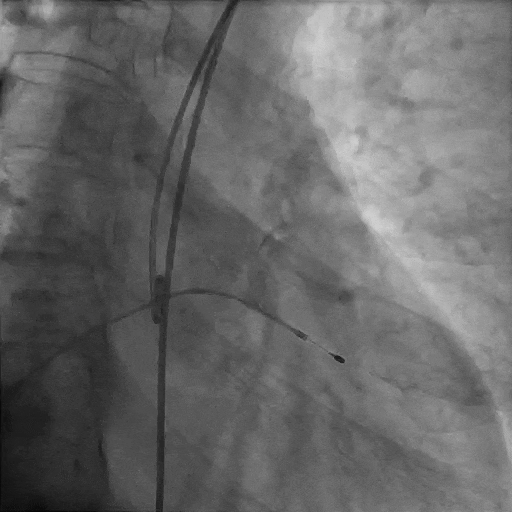

主动脉根部造影

导丝跨瓣

球囊预扩